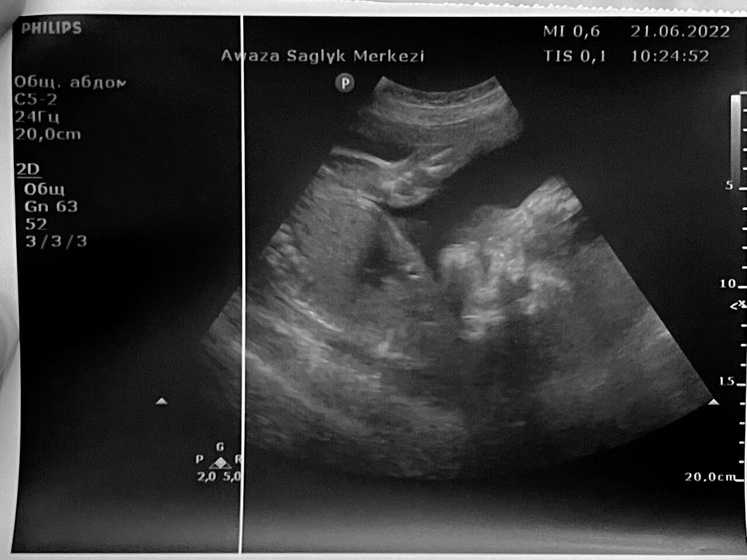

Сходила сегодня на доплер. Море впечатлений. Главное, что все хорошо, ни каких отклонений нет. Пуповина в порядке, кровоток в порядке, гипоксии нет. Обвитий нет. Воды чисты ( в прошлый скрининг были мутные из-за болезни)…. Весит мое чудо уже 745г….Потанцевал там прям в датчик))) даже показал как умеет ? зевать)))) это очень милооо))) сидит на попе, надеюсь ещё перевернётся.